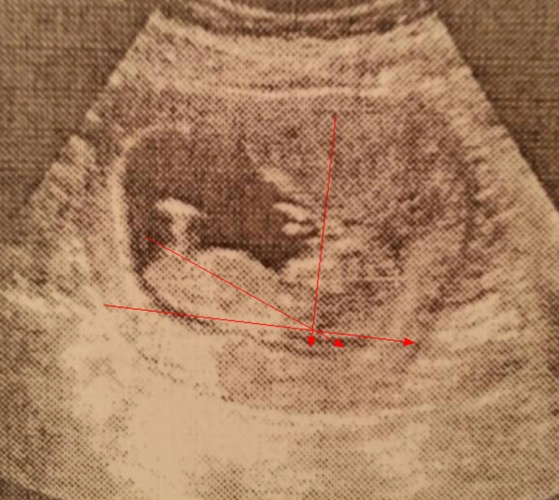

12周nt顺利通过!感恩!

nt看男女

看男女,nub(nub theory)是英国开始流传起来的,nub就是胎儿的生殖节